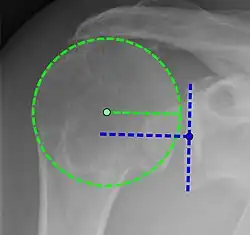

Рентгеновская проекционная рентгенография не может напрямую выявить разрывы вращающей манжеты, «мягких тканей», и, следовательно, обычные рентгеновские лучи не могут исключить повреждение манжеты. Однако косвенные доказательства патологии можно увидеть в случаях, когда одно или несколько сухожилий подверглись дегенеративной кальцификации (кальцифицирующий тендинит). Головка плечевой кости может мигрировать вверх (высоко расположенная головка плечевой кости) вследствие разрыва подостной или комбинированной надостной и подостной мышцами.[44] Миграцию можно измерить расстоянием между:

- Линией, пересекающая центр линии между верхним и нижним краями суставной поверхности суставной впадины (синяя на изображении).

- Центром наиболее подходящего круга, расположенный над суставной поверхностью плечевой кости (зеленый на изображении)

Обычно первый расположен ниже второго, и поэтому переворот указывает на разрыв вращательной манжеты.[44] Длительный контакт между высоко расположенной головкой плечевой кости и акромионом над ней может привести к обнаружению на рентгеновских снимках износа головки плечевой кости и акромиона или вторичного дегенеративного артрита плечевого сустава, называемого артропатия манжеты.[43] Случайные рентгенологические находки костных шпор в соседнем акромиально-ключичном суставе могут показать костную шпору, растущую от внешнего края ключицы вниз к вращающей манжете. На нижней стороне акромиона также можно увидеть шпоры, которые, как когда-то считали, вызывают прямое истирание вращающей манжеты из-за контактного трения, концепция, которая в настоящее время считается спорной.